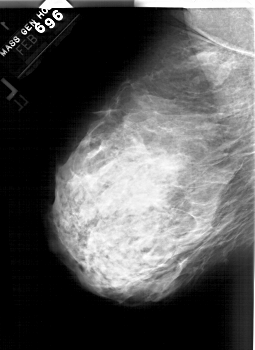

ics_version 1.0 filename A-1564-1 DATE_OF_STUDY 6 2 1996 PATIENT_AGE 43 FILM FILM_TYPE REGULAR DENSITY 4 DATE_DIGITIZED 14 9 1998 DIGITIZER HOWTEK 43.5 SEQUENCE LEFT_CC LINES 6331 PIXELS_PER_LINE 4156 BITS_PER_PIXEL 12 RESOLUTION 43.5 NON_OVERLAY LEFT_MLO LINES 5941 PIXELS_PER_LINE 4321 BITS_PER_PIXEL 12 RESOLUTION 43.5 NON_OVERLAY RIGHT_CC LINES 6226 PIXELS_PER_LINE 4261 BITS_PER_PIXEL 12 RESOLUTION 43.5 OVERLAY RIGHT_MLO LINES 6271 PIXELS_PER_LINE 4501 BITS_PER_PIXEL 12 RESOLUTION 43.5 OVERLAY |